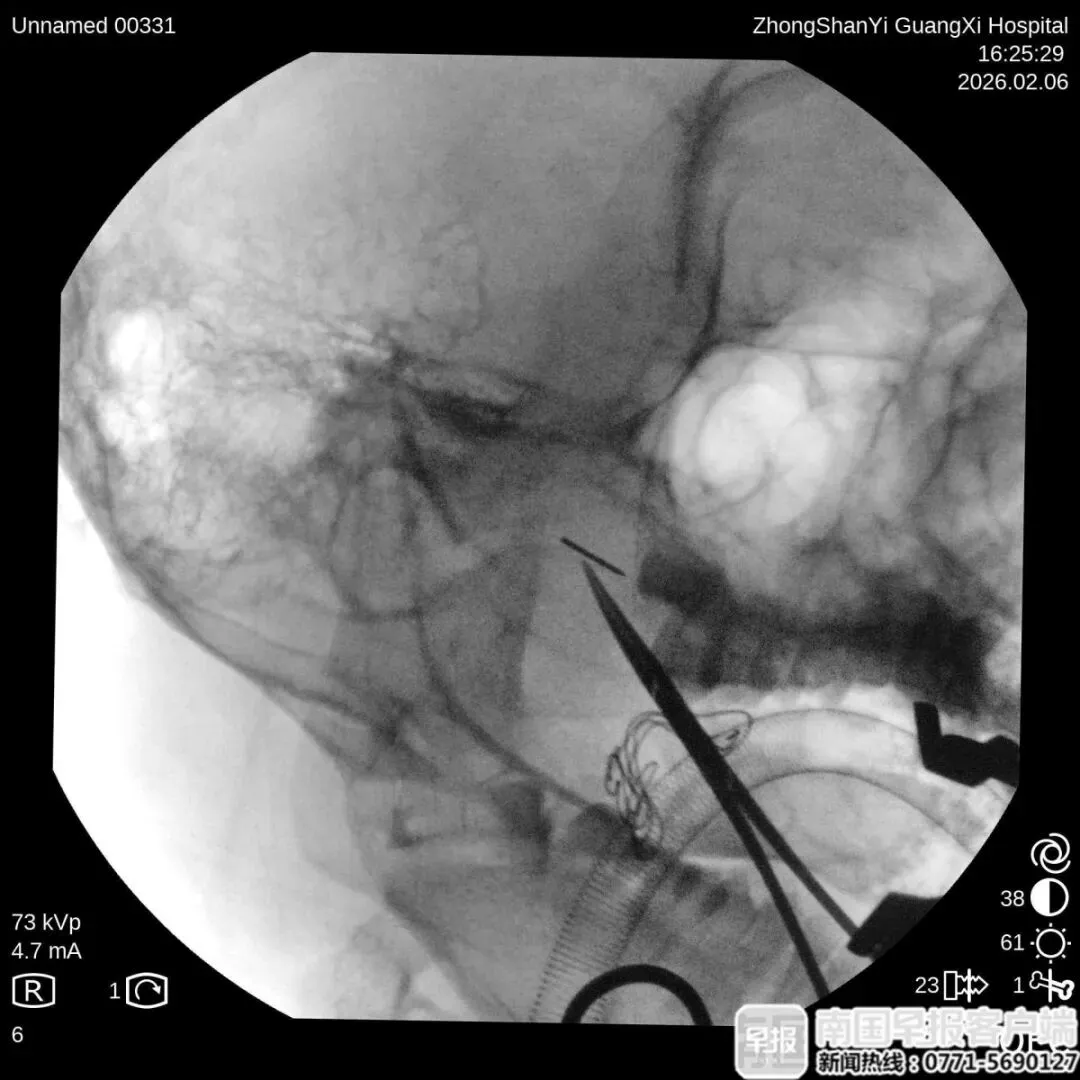

手术中使用移动C臂X射线机进行多角度定位。院方供图

最终,团队为阿诺制订了个性化治疗方案,在气管插管全麻下,借助C臂X射线机多角度定位,为了防止断针跟随面部的软组织移动,团队使用高强度磁铁将断针固定,花了30分钟,经口实施手术成功取出断针。